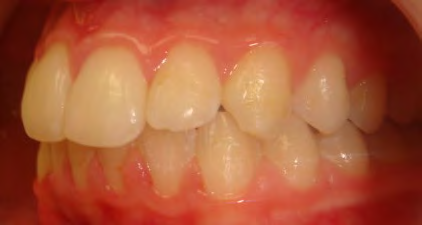

Below are cases treated at Vakresmil without extractions within the last three years. The families had been told, “It is simply not possible for your child to be treated without extractions” by orthodontists. Judge for yourself if that was right or wrong.

The overall aim is to produce the best smile we can — a “beautiful smile”, if you will — without premolar extractions, headgear, facemasks or banded appliances. A smile that both the patient and we at Vakresmil can be proud of.